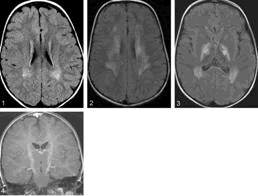

Joe Pepitone (JP) Neuro-radiólogo. La resonancia cerebral magnética (MRI) mostró cambios atróficos mínimos, sobre todo en la corteza motora, sin lesiones de la sustancia blanca. El MRI de la columna confirmó una atrofia medular difusa sin siringomielia.

La Resonancia muestra leucodistrofia (Figura 5).

El SSL es causado por mutaciones del gen ALDH3A2 que codifica la enzima dehidrogenasa de aldehidos grasos (FALDH). Existe acumulación secundaria de alcoholes grasos de cadena larga con trastorno secundario del metabolismo celular. La epidermis pierde la barrera acuosa causando la ictiosis. El metabolismo anormal del leucotrieno B4 (LTB4) precipita el prurito. la escanografía cerebral (TAC) muestra atrofia cortical. El MRI señala hipomielinización congénita y/o demielinización adquirida mientras que el Espectroscopio de Resonancia Magnética demuestra acumulación de lípidos anormales alrededor de los ventrículos. El EEG puede registrar ondas epilépticas de punta y onda generalizadas en un trazado de fondo lento e irregular. El diagnostico de SSL se puede confirmar midiendo la LTB-4 y sus metabolitos en la orina.